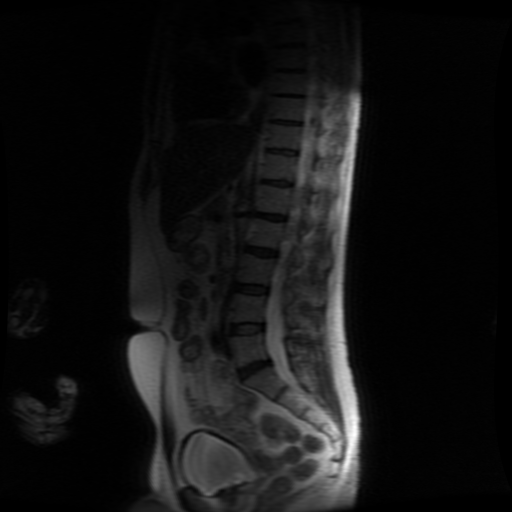

Bild uppladdad av Björn

Fick svaret från radiolog idag efter MR av underben och ländrygg. Tips på infasning? Någon som är bra på medicinska termer?

visar en bild av ländryggen, på L5 eller L4 ser det verkligen ut som en buktning men står inget om detta i utlåtandet.

MR ländrygg visar inga diskbråck, ingen spinal stenos eller rotpåverkan. Endast lätt dehydrering i disk L5-S1 med diskreta Modic typ 2-förändringar utan ödem.

MR vänster underben visar ett cirka 1 × 1 × 1 cm stort intramedullärt ödem i tibia, beläget mittdiafysärt, utan kortikalt eller periostalt engagemang. Mjukdelar u.a. Bilden förenlig med liten intramedullär stressreaktion.